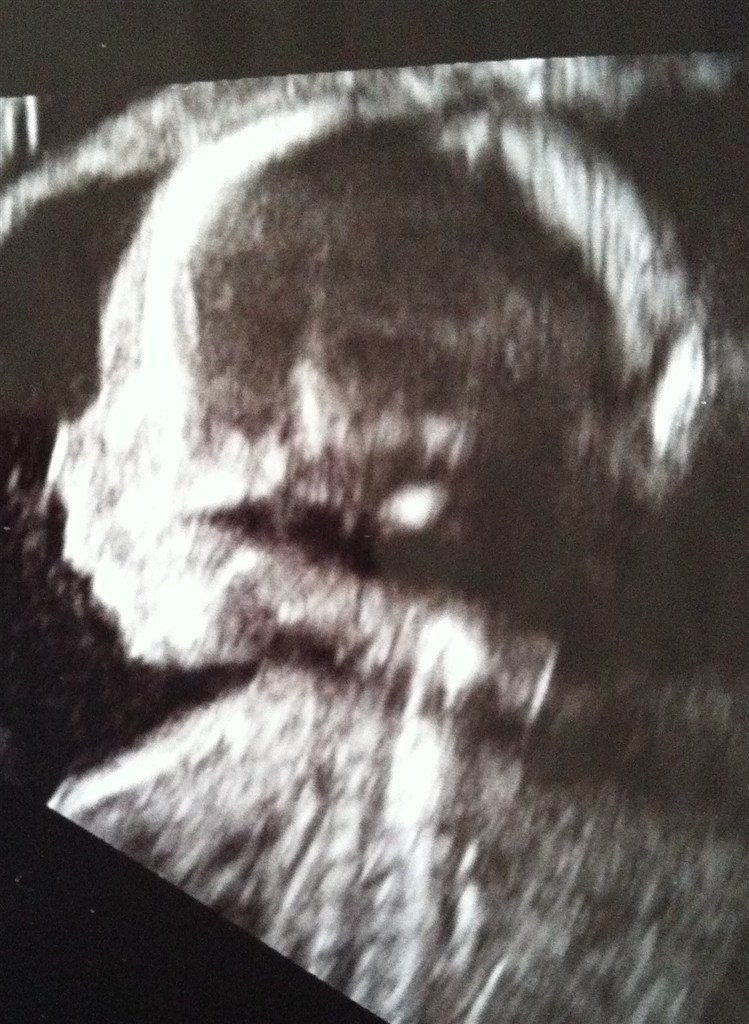

Nu havde jeg set det hele og det var billedet af de 4 hjertekamre der drillede